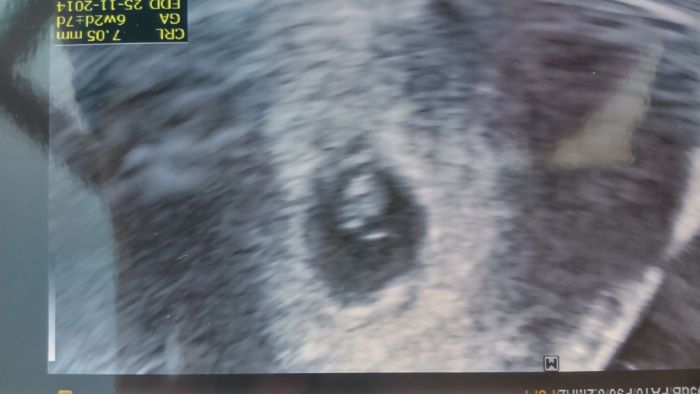

Ahoj holky, tak jsem po kontrole. Prcek má 7mm a odpovídá 6+2 takže se vracím o 14dní zpět až budu na pc tak si upravím metřík píšu z mobilu. Jinak srdíčko krásně tluče :-D a 23.4. Si jdu pro průkazku. Přidávám fotku